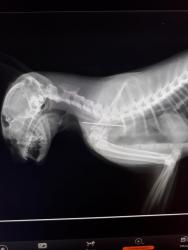

В ветеринарную лечебницу № 1 обратилась женщина, чья кошка сильно кашляла. По словам хозяйки, животное прошло курс лечения в другой клинике по поводу бронхопневмонии, но так и не выздоровела. В ходе диагностики был сделан снимок, на котором было ясно видно, что в мягких тканях шейно-грудного отдела между пищеводом и трахеей находилась игла.